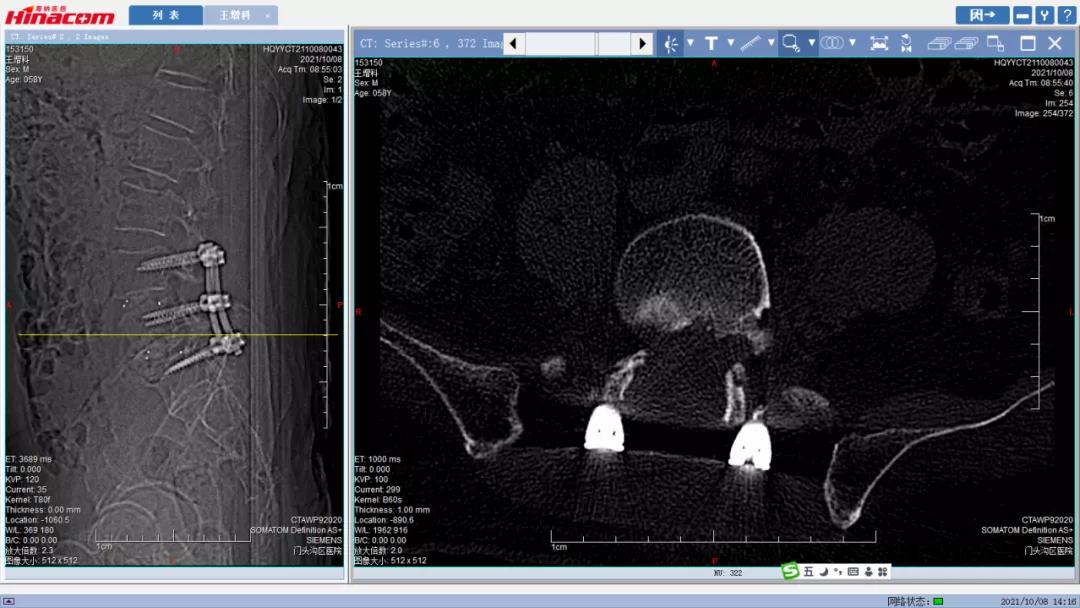

经匡正达主任诊治后,发现患者有先天性腰椎骶化,极易误诊,如果间隙做错了,那后果不堪设想。又考虑到患者要干农活,如果单纯椎管减压,有术后不稳的可能,而且患者长期生理性脊柱侧弯,综合考虑,最终决定为患者实施腰椎管减压的同时,进行椎间植骨融合钉棒内固定术。

手术于2021年9月26日顺利实施。术后,患者十几年来的下肢麻木疼痛和跛行终于消失了! 可以堂堂正正的走路,让王某一下显得年轻了十几岁!